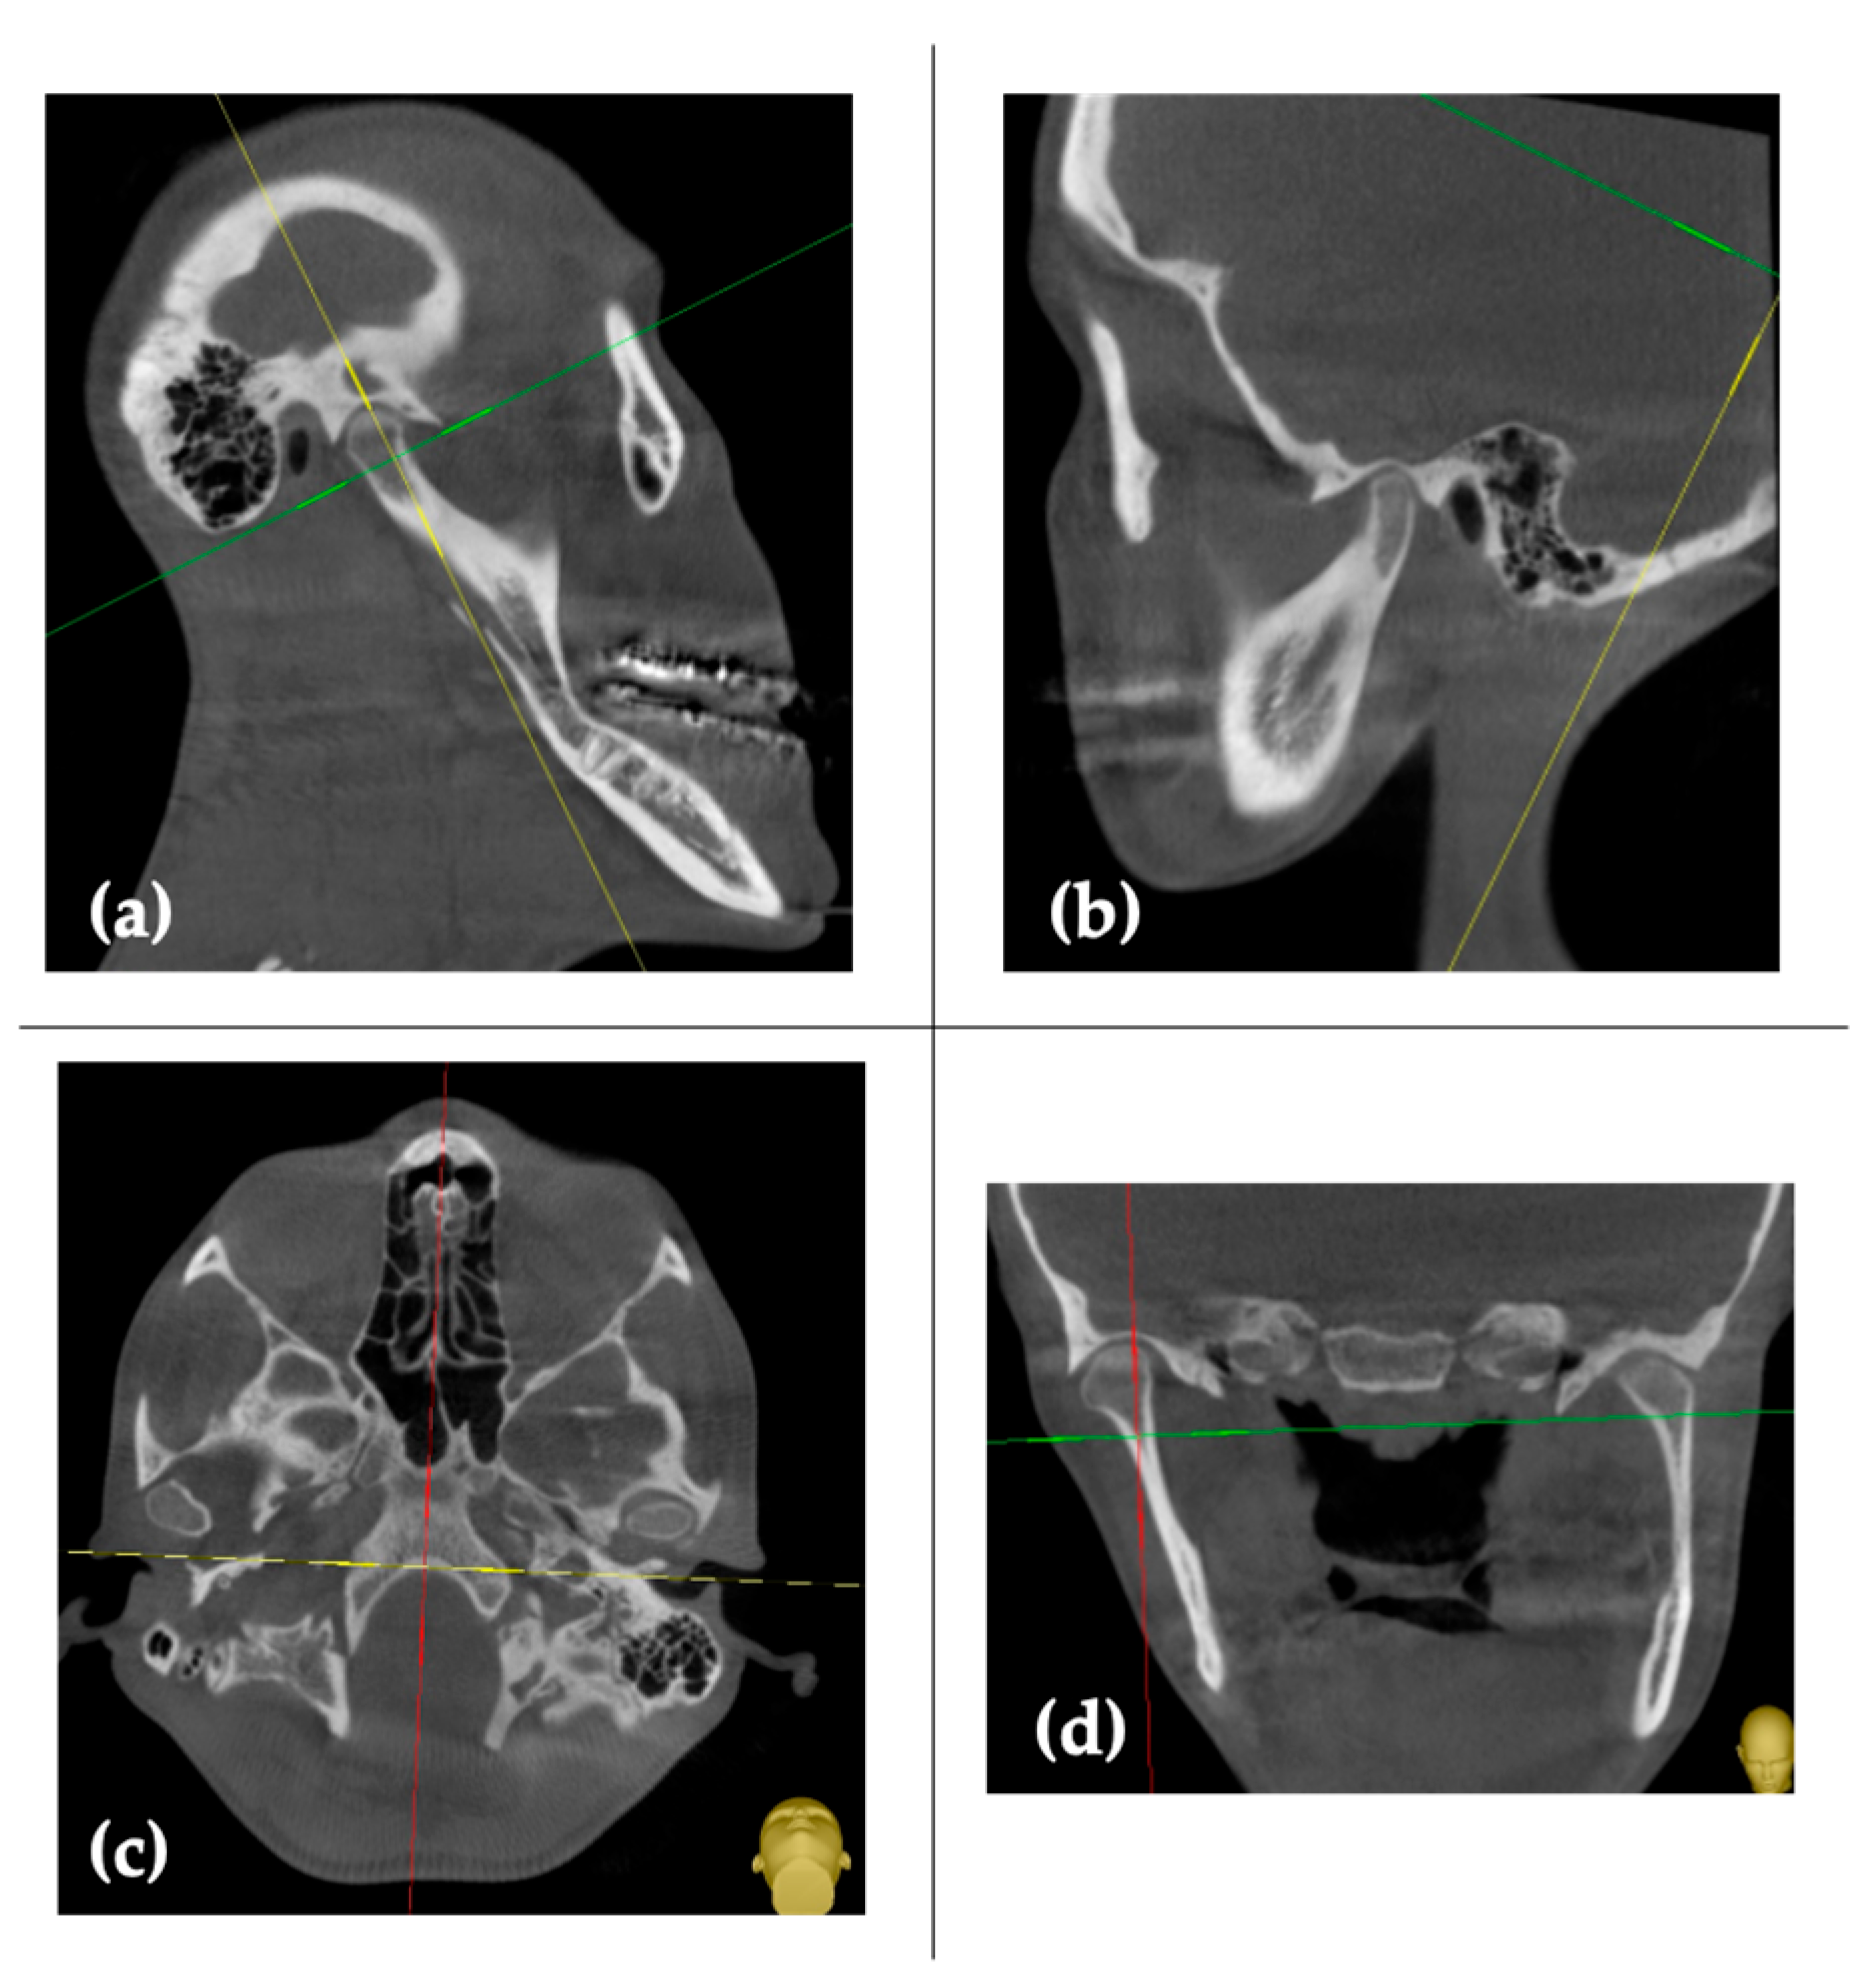

2. Case Report